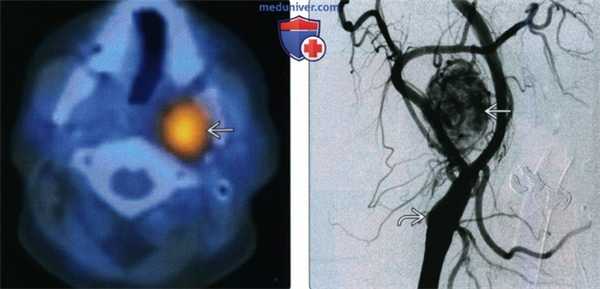

(Слева) SPECT/KT, аксиальная проекция, через 11 часов после введения индий-111 - октреотида. Крупный участок повышенной активности в верхних отделах левого сонного пространства. Этот радиофармпрепарат связывается с соматостатиновыми рецепторами, которые экспрессируют параганглиомы.

(Справа) Ангиография, артериальная фаза. Интенсивное раннее накопление контраста в сосудах опухоли с множественными крупными питающими сосудами. Опухоль расположена над областью бифуркации, поэтому ее расширения не наблюдается.